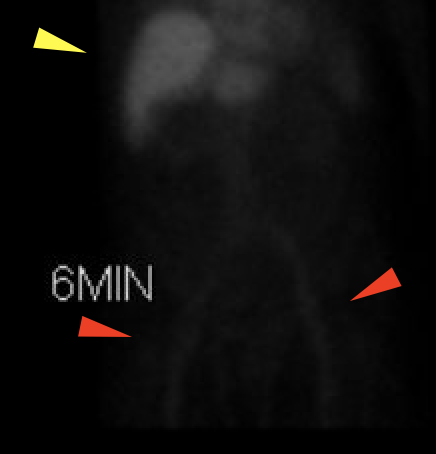

Age: 85

Sex: Male

Indication: Concern for ascending cholangitis

Radiotracer: Tc99m Mebrofenin

Sample ReportFindings consistent with acute cholecystitis.

Additional findings suggesting hepatic dysfunction.